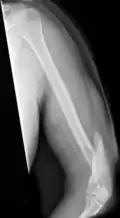

Humerus fracture

| Midshaft humerus fracture with callus formation | |

A humerus fracture is a break of the humerus bone in the upper arm.[1] Symptoms may include pain, swelling, and bruising.[1] There may be a decreased ability to move the arm and the person may present holding their elbow.[2] Complications may include injury to an artery or nerve, and compartment syndrome.[2]